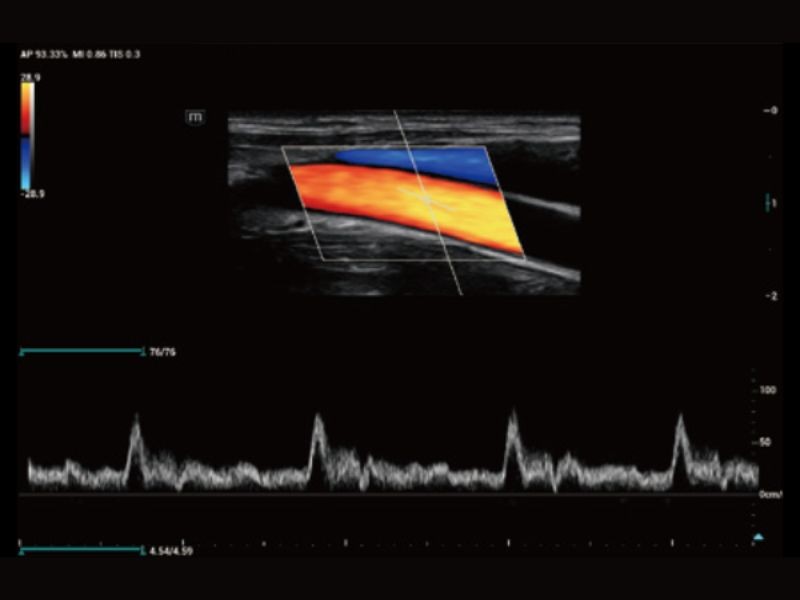

RIMT

Medição IMT em tempo real baseada em dados de RF

R-VQS

Coeficiente de dureza vascular e velocidade da onda de pulso (PWV)